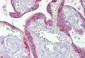

ApplicationWB, IHC-P

ReactivityH, M, Rat, (Pig), (C), (Hs), (B)

AccessionP61812